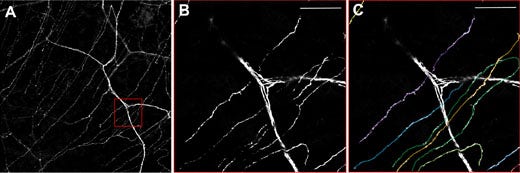

Figure 3: Neurones in the cornea of a thy1-YFP mouse.

A) Overview showing the thicker stromal nerves and the finer nerves of the subbasal plexus. B)

Zooming in on the red box and C) Quantification of single subbasal nerves. Using the FV10i, 60x oil objective. Scale bar 50 μm.